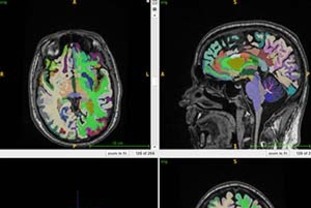

[문화투데이 구재숙 기자] 새해 담배를 끊겠다는 결심이 '작심삼일'(作心三日)로 끝나지 않으려면 이번 주말을 잘 넘겨야 한다. 금단 현상은 사흘째 최고조에 이르는 경우가 많아 이때를 가장 주의해야 한다. 개인의 의지만으로는 금연에 성공하기 쉽지 않으므로 전문가 등 주위의 도움을 받는 것도 적극적으로 고려해볼 만하다. 3일 의료계에 따르면 흡연은 단순한 기호 식품을 소비하는 게 아니라 니코틴이 뇌의 보상 회로를 지배하는 일종의 중독으로 봐야 한다. 금연으로 인해 니코틴 공급이 끊기면 뇌는 신경 회로의 변화로 인해 극심한 불안과 초조함을 유발한다. 즉, 뇌에 있는 니코틴 수용체가 지속적인 니코틴을 원하므로 갑자기 공급이 중단되면 불안, 초조, 짜증 등 금단 현상이 나타난다. 니코틴에 의한 금단 현상은 흡연자가 마지막 담배를 피운 지 2시간 이내에 발생하기 시작해 24∼48시간쯤에 최고에 이른다. 짧게는 수 주 또는 수개월까지 이러한 금단 현상이 지속할 수 있다. 이미 니코틴에 중독된 상태에서는 개인의 의지만으로 금연하기가 쉽지 않다. 아무리 강한 정신력을 갖췄더라도 뇌가 보내는 강력한 화학적 신호를 혼자서 억누르기가 어렵기 때문이다. 약물 치료나 전문가와의 상담